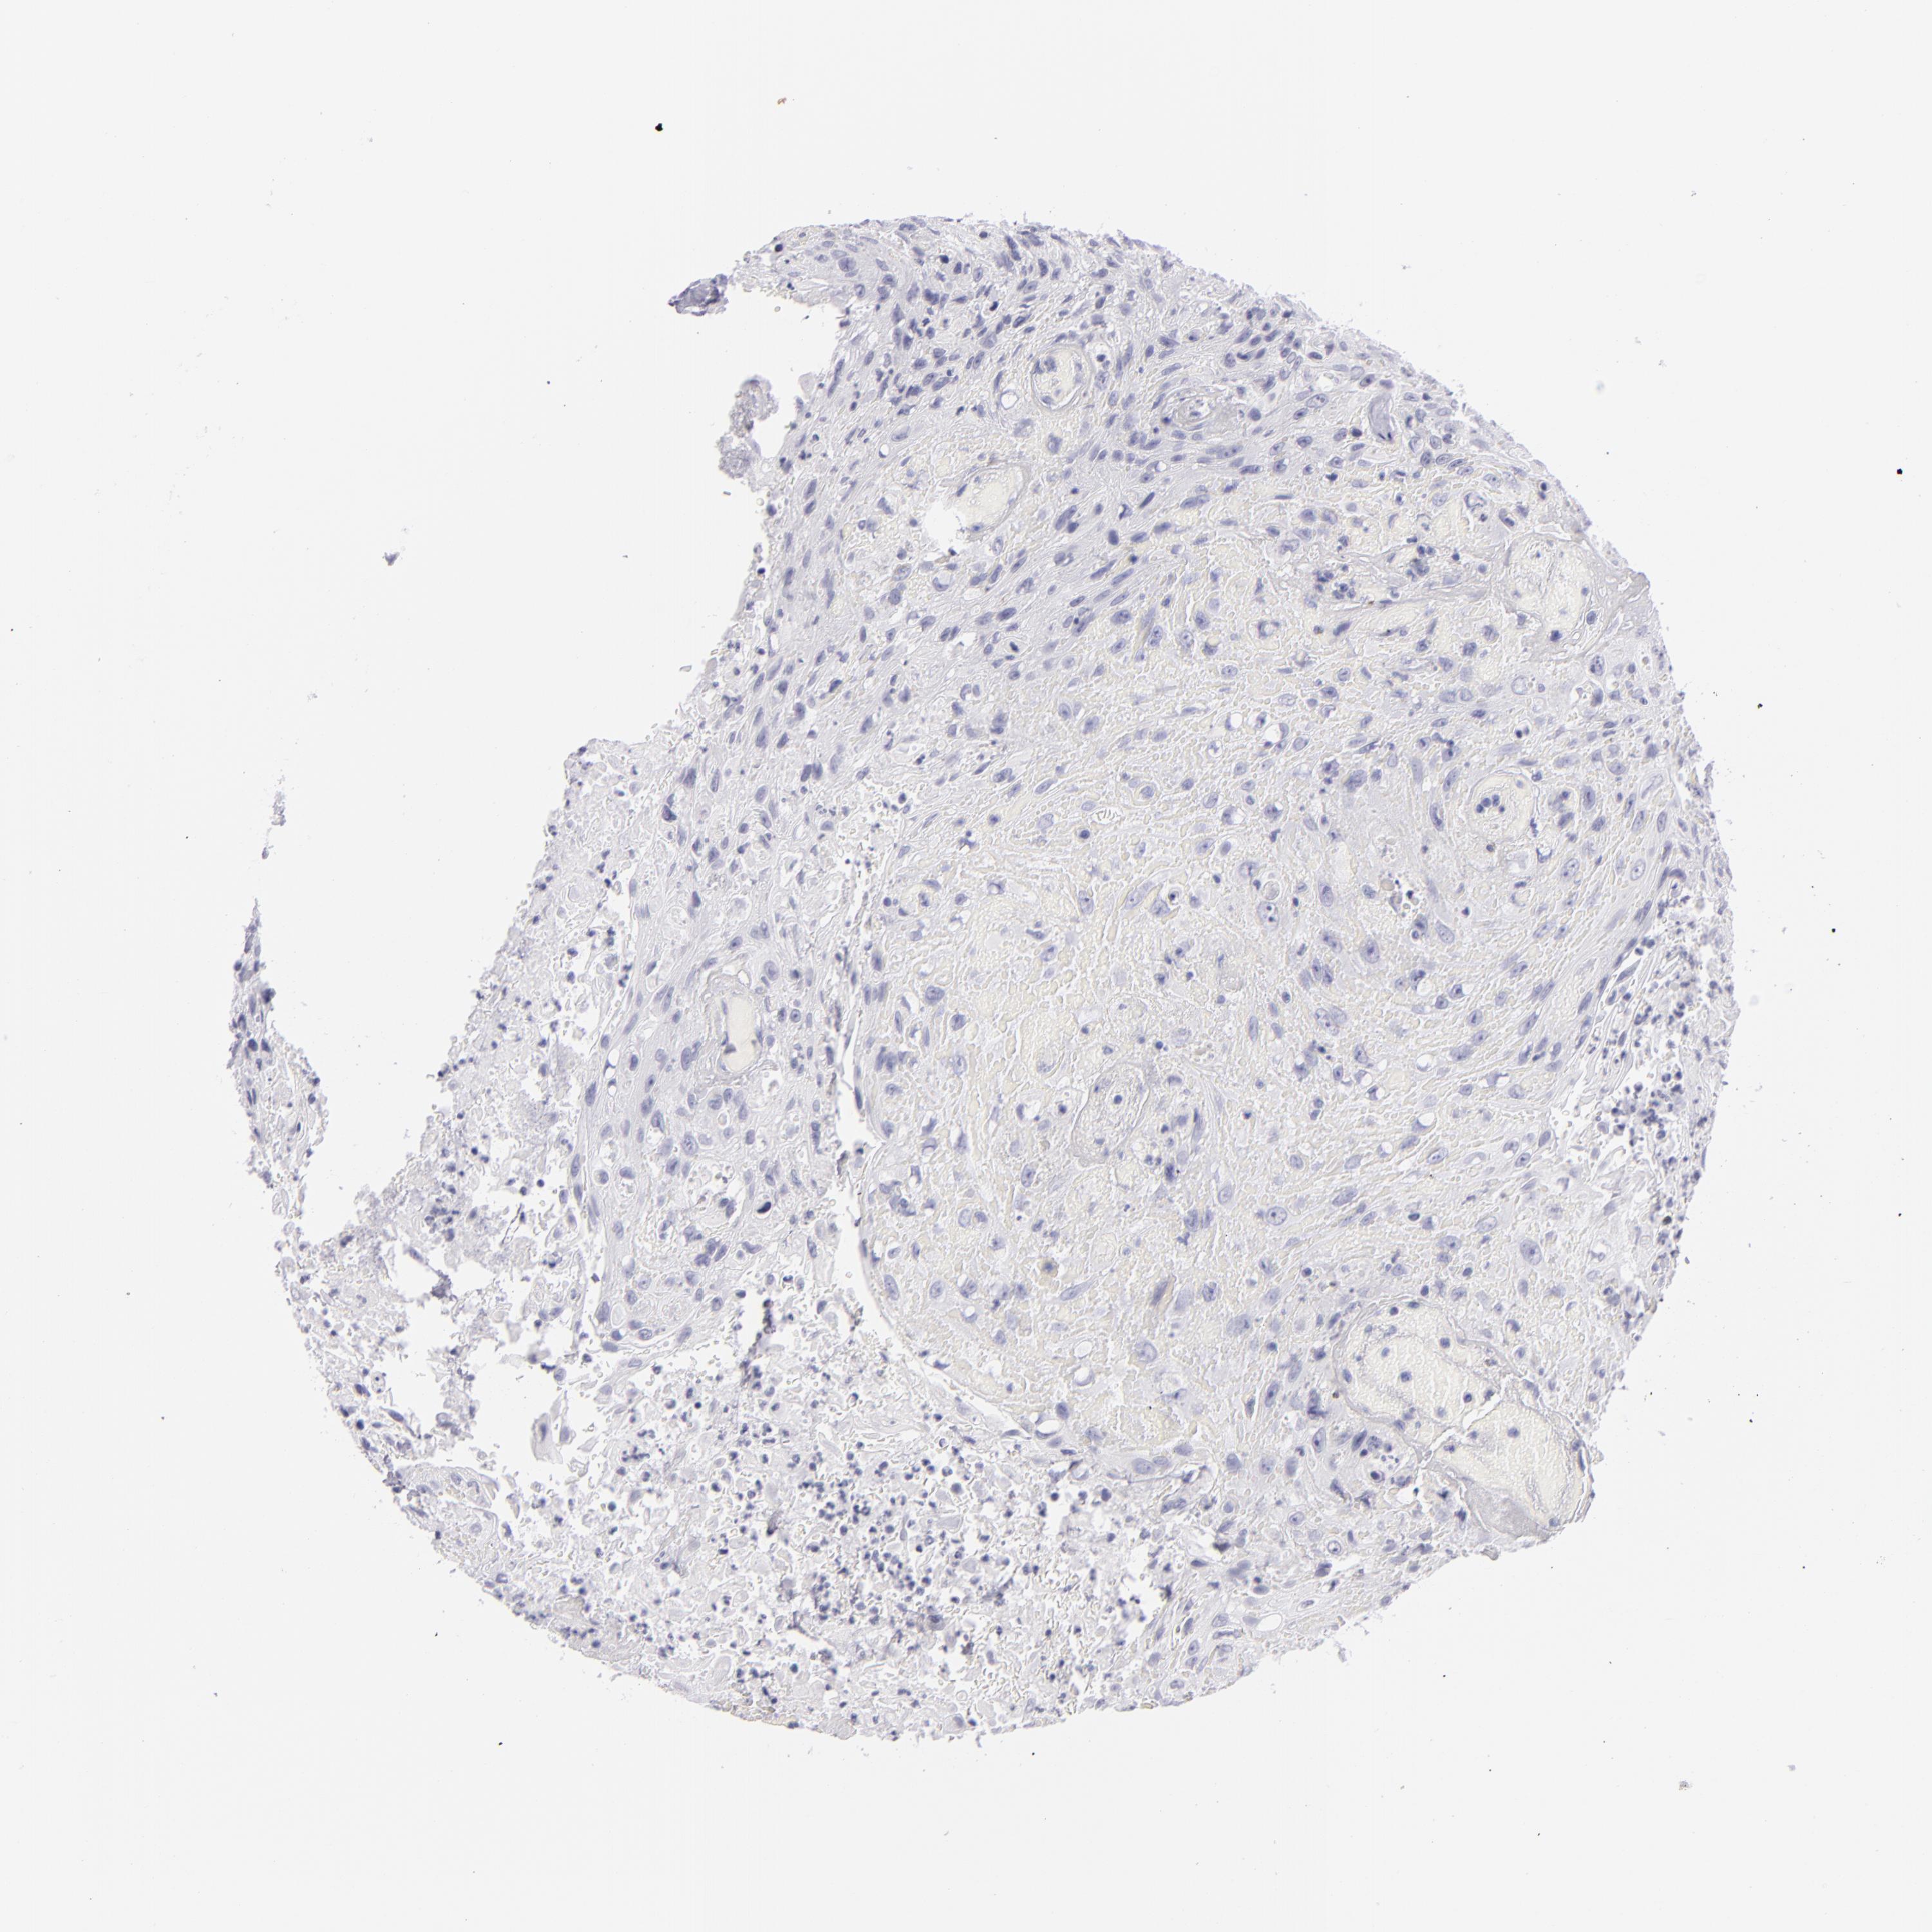

UROTHELIAL CANCER - Protein expressioni

A mouse-over function shows sample information and annotation data. Click on an image to view it in a full screen mode. Samples can be filtered based on level of antibody staining by selecting one or several of the following categories: high, medium, low and not detected. The assay and annotation is described here.

Note that samples used for immunohistochemistry by the Human Protein Atlas do not correspond to samples in the TCGA dataset.

Antibody stainingi

Antibody staining in the annotated cell types in the current human tissue is reported as not detected, low, medium, or high, based on conventional immunohistochemistry profiling in selected tissues. This score is based on the combination of the staining intensity and fraction of stained cells.

Each image is clickable and will lead to virtual microscopy that enables deeper exploration of all samples and also displays staining intensity scores, fraction scores and subcellular localization as well as patient and tissue information for each sample.

Antibody HPA006884

Antibody HPA006885

Antibody CAB002452

Urothelial carcinoma, Low grade

Urothelial carcinoma, High grade

Adenocarcinoma, NOS